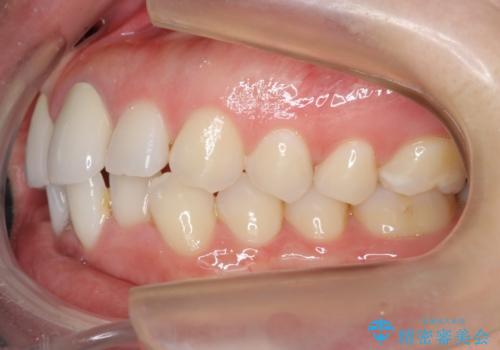

終了時

矯正終了後、1年ほど保定を行いました。

その後、マージンが舌側が深い状態だったため、歯ぐきの手術(歯周外科処置:APF)を行ってから最終的なセラミックを装着しました。